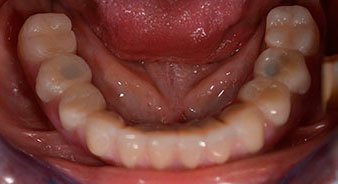

Nach der Zeit, die für die Osseointegration benötigt wird, kann die endgültige Abformung der Implantate erfolgen und entsprechend die endgültige Arbeit angefertigt werden (Abb. 19 und 20). Hier können Behandler und Patient gemeinsam entscheiden, ob diese eine Keramik- oder Kunststoffverblendung, ein Zirkon- oder Metallgerüst bekommen soll. Im vorliegenden Fall hat sich das Team um Dr. Pascu, aufgrund der unklaren Prognose der Oberkieferbezahnung und des elongierten Zahnes 24, für eine Kunststoffverblendung entschieden. Diese ist im Allgemeinen wesentlich einfacher umzustellen und der neuen Situation im Oberkiefer anzupassen.